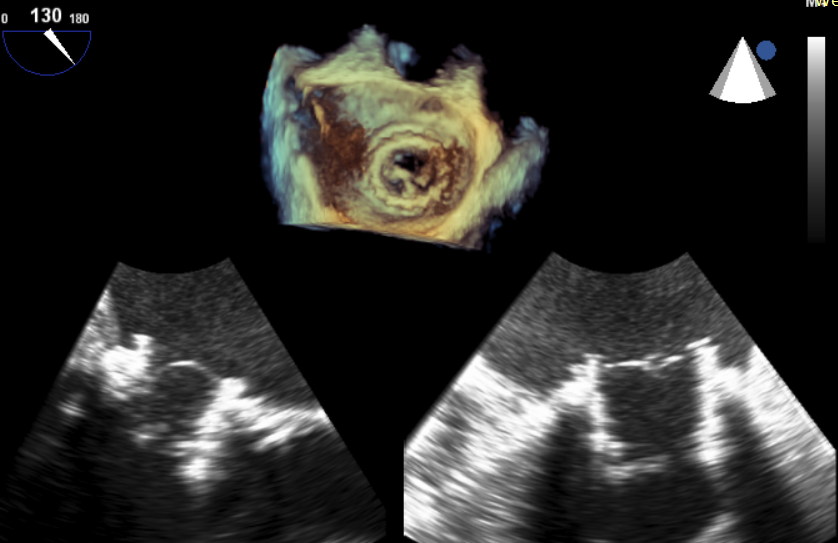

患者,男,70岁,于1月前无明显诱因下出现活动后胸闷,步行100米后出现气促伴双下肢乏力,无胸痛、发热、头晕头痛、发热畏寒、恶心呕吐及咳嗽等不适。患者于7年前行二尖瓣生物瓣置换术(Edwards Perimount 27#)。术前心脏超声提示:二尖瓣生物瓣置换术后:生物瓣重度狭窄(有效瓣口面积0.58cm²,MPG=12mmHg);左房增大(57mm)左室增大(舒张末前后径73mm),左室壁静息状态下运动弥漫性减弱,左室收缩功能明显减低(EF=29%,Simpson法);轻度肺动脉高压;术前心功能IV级。

原生物瓣少量反流

过瓣流增快,呈“五彩状”